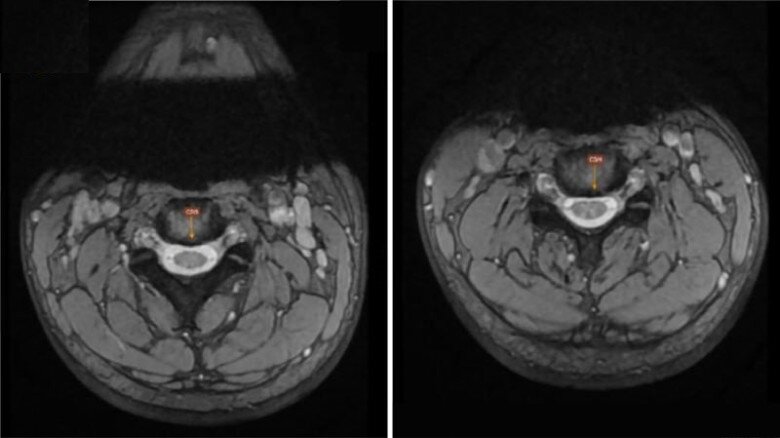

ThS.BS Nguyễn Thị Huyền Thu - Chuyên khoa Thần kinh, trực tiếp thăm khám cho bệnh nhân N cho biết, qua khai thác tiền sử, nam thanh niên chia sẻ có thói quen dùng bóng cười một năm nay, với tần suất khoảng 3 lần/tuần. Qua chia sẻ của người bệnh, bác sĩ đã chỉ định cho chụp cộng hưởng từ, kết quả cho thấy người bệnh bị thoái hóa đĩa đệm cột sống cổ, viêm đa dây thần kinh ngoại biên. Bác sĩ kết luận nguyên nhân gây tê bì tứ chi của bệnh nhân đến từ việc lạm dụng bóng cười kéo dài, hậu quả do ngộ độc khí N2O dẫn tới tổn thương thần kinh.

Hình ảnh chụp cộng hưởng từ cổ cho thấy bệnh nhân có thoái hóa đĩa đệm cột sống cổ. Ảnh: BSCC.